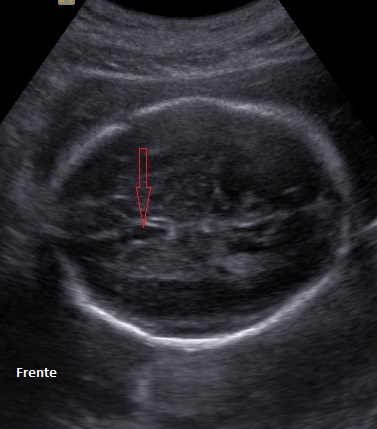

Las estructuras intracraneales después de la semana 18-20 del embarazo son muy características y permanecen visualmente invariables hasta el final del embarazo, solo modificando sus tamaños a medida que el feto crece. Esto es de gran ayuda ya que permite determinar la aparición de cambios que podrían sugerir desviación de la normalidad y aparición de una malformación congénita o lesión adquirida por eventos externos especialmente relacionados a infecciones y accidentes vasculares fetales.

En este resúmen gráfico se incluye la mayor parte de las lesiones cerebrales congénitas visibles en vida fetal; los cortes transversales expuestos aquí son insuficientes para algunas de ellas y los hallazgos pueden modificarse en el tiempo, usualmente manifestando mayor número de elementos anómalos. Muy pocas condiciones mejoran con el tiempo